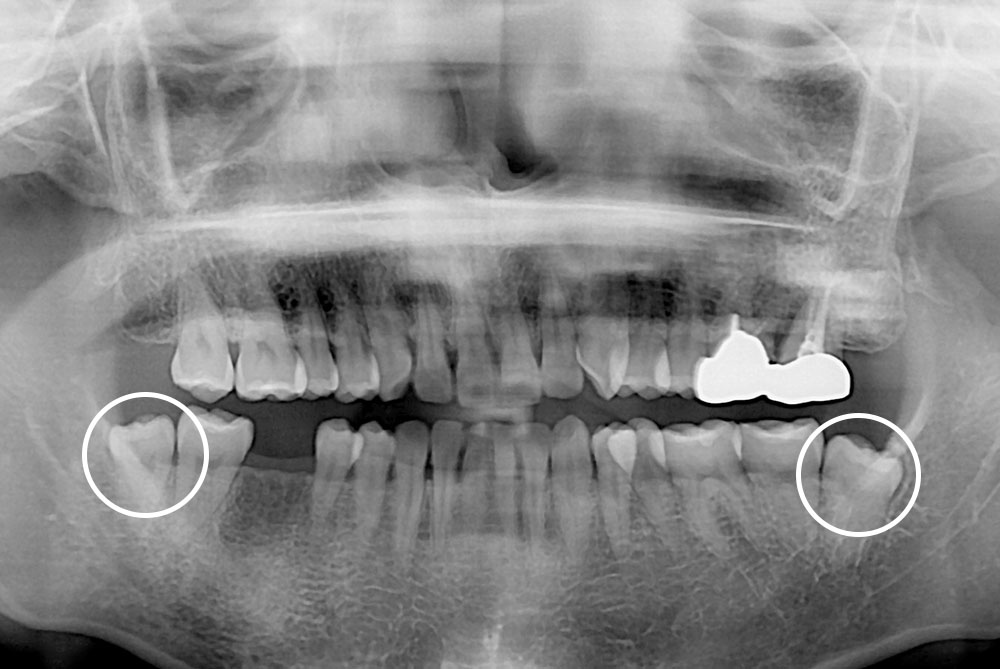

[사랑니] 매복 사랑니 발치

치료후 : 2021-12-15

세종치과는 구강악안면외과학 박사이신 원장님이 발치하는 치과입니다.